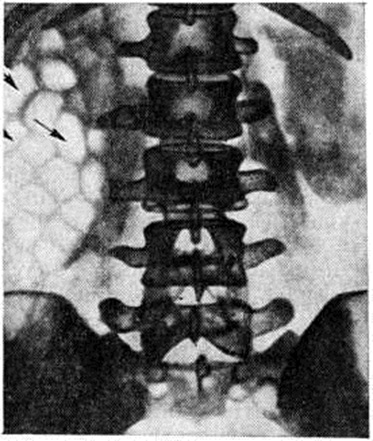

Рис. 2.

Обзорная рентгенограмма брюшной полости и таза при эмфизематозном пиелонефрите: в проекции правой почки видны множественные газовые пузыри неправильной формы (указаны стрелками).

Эмфизематозный пиелонефрит — одна из форм острого гнойного Пиелонефрит Наблюдается преимущественно у больных сахарным диабетом, несколько чаще у женщин. Возбудителями являются кишечная палочка, В. aerogenes, протей, стафилококк и другие Возникновению эмфизематозного Пиелонефрит способствуют наличие в организме анаэробных микроорганизмов, обструкция мочевых путей. Заболевание обычно поражает одну почку и нередко сочетается с некрозом почечных сосочков, тромбозом почечной вены. Характерен некроз паренхимы почки с образованием газа внутри органа и в околопочечной клетчатке. Высокое содержание глюкозы в крови при сахарном диабете является дополнительным фактором, обусловливающим выработку углекислого газа. Болезнь протекает тяжело, сопровождается состоянием, напоминающим ступор, интоксикацией, почечной недостаточностью, высокой температурой, сильными болями в поясничной области, лейкоцитозом, Лейкоцитурией, бактериурией. Моча имеет резко кислую реакцию. В распознавании эмфизематозного Пиелонефрит большую роль играют рентгенологическое методы исследования, в частности обзорный снимок, компьютерная томография. На рентгенограмме в проекции почки видно скопление теней газовых пузырей (рисунок 2). При бактериологические исследовании мочи находят газообразующие микроорганизмы.